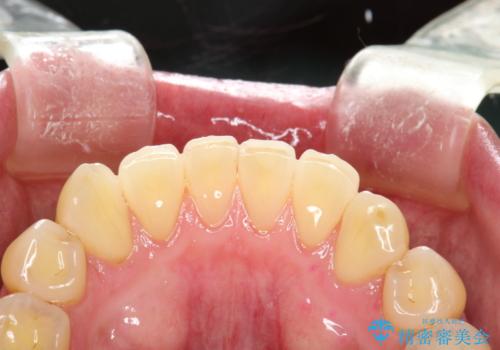

- 半年ぶりの来院できれいにクリーニンングしてほしいとのことでした。染め出しをして歯磨きチェックとPMTC30分コースを行いました。

歯の染め出しとは、汚れがついている部分に色が着いて、どの部分が磨けていないか分かりやすく確認することができます。歯の表面についているプラークは歯と同じ色をしているので見た目では分かりにくいものです。そのため、染め出しをすると、長い期間付着している汚れが濃い色になったり、どの部分が苦手で磨き残してしまっているか確認することが出来ます。